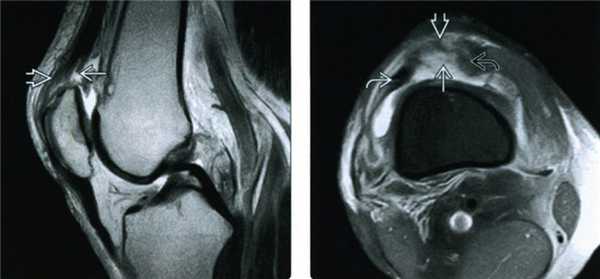

Когда МРТ коленного сустава лучше, чем КТ?

МРТ коленного сустава также дает возможность получить трехмерную визуализацию колена и череду снимков, которые возможно посмотреть в отдельности, но здесь, в отличие от КТ, не используются рентгеновские лучи, и пациент не получает никакой дозы облучения. Для диагностического сканирования используется действие электромагнитных волн. В трубе томографа находятся большие магниты. Внутрь трубы помещается человек. Когда магниты включаются, создается электромагнитное поле. Частички организма пациента с содержанием воды начинают колебаться и излучать энергию. Эту энергию улавливает специальный компьютер. Таким образом магнитно-резонансный томограф рисует всю картину состояния мягких тканей и хрящей колена. Визуализация снимков на МРТ разносторонняя. Это необходимо для наиболее полного и точного осмотра коленного сустава и соседних структур.

Посредством магнитно-резонансной томографии лучше, чем с помощью КТ, видны мышцы, сухожилия, мениски, сосудистое русло и нервные окончания. МРТ коленного сустава будет приоритетным методом обследования, если есть подозрения на:

- отрыв, разрыв, надрыв тканей;

- поражение мениска;

- воспаление суставных поверхностей;

- кисты и опухолевые образования в суставной сумке;

- инфекционные поражения мягких тканей, нагноения, абсцессы.

Магнитно-резонансная томография является методом выбора в вопросах диагностики кисты подколенной области или кисты Бейкера. Она позволяет достоверно выявлять характер сопутствующих внутрисуставных патологических изменений в коленном суставе, проводить дифференциальную диагностику, уточнять особенности анатомического строения и расположения кисты в подколенной ямке, а также локализацию ее соустья. Магнитно-резонансная томография при травмах коленного сустава позволяет с точностью до 90% оценить степень повреждения, сократить сроки постановки диагноза и тем самым увеличить эффективность лечения травматических повреждений коленного сустава.